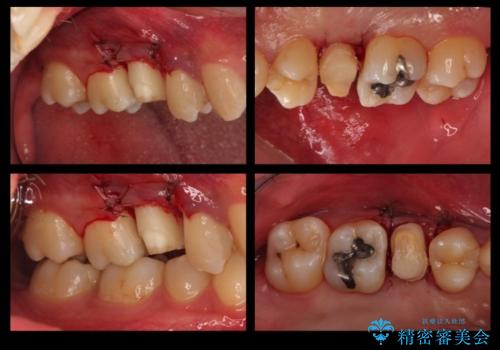

歯の健康な部分を矯正治療で引っ張り出してから、虫歯治療を行なっています。

- 32万円(右上5:ジルコニアクラウン(スペシャル)10万円、仮歯 1万円、エクストリュージョン:10万円、歯周外科治療:エクストリュージョン費用に含む 根管治療:9万円 ファイバーコア:2万円)費用は治療当時の料金となります

治療途中

終了時